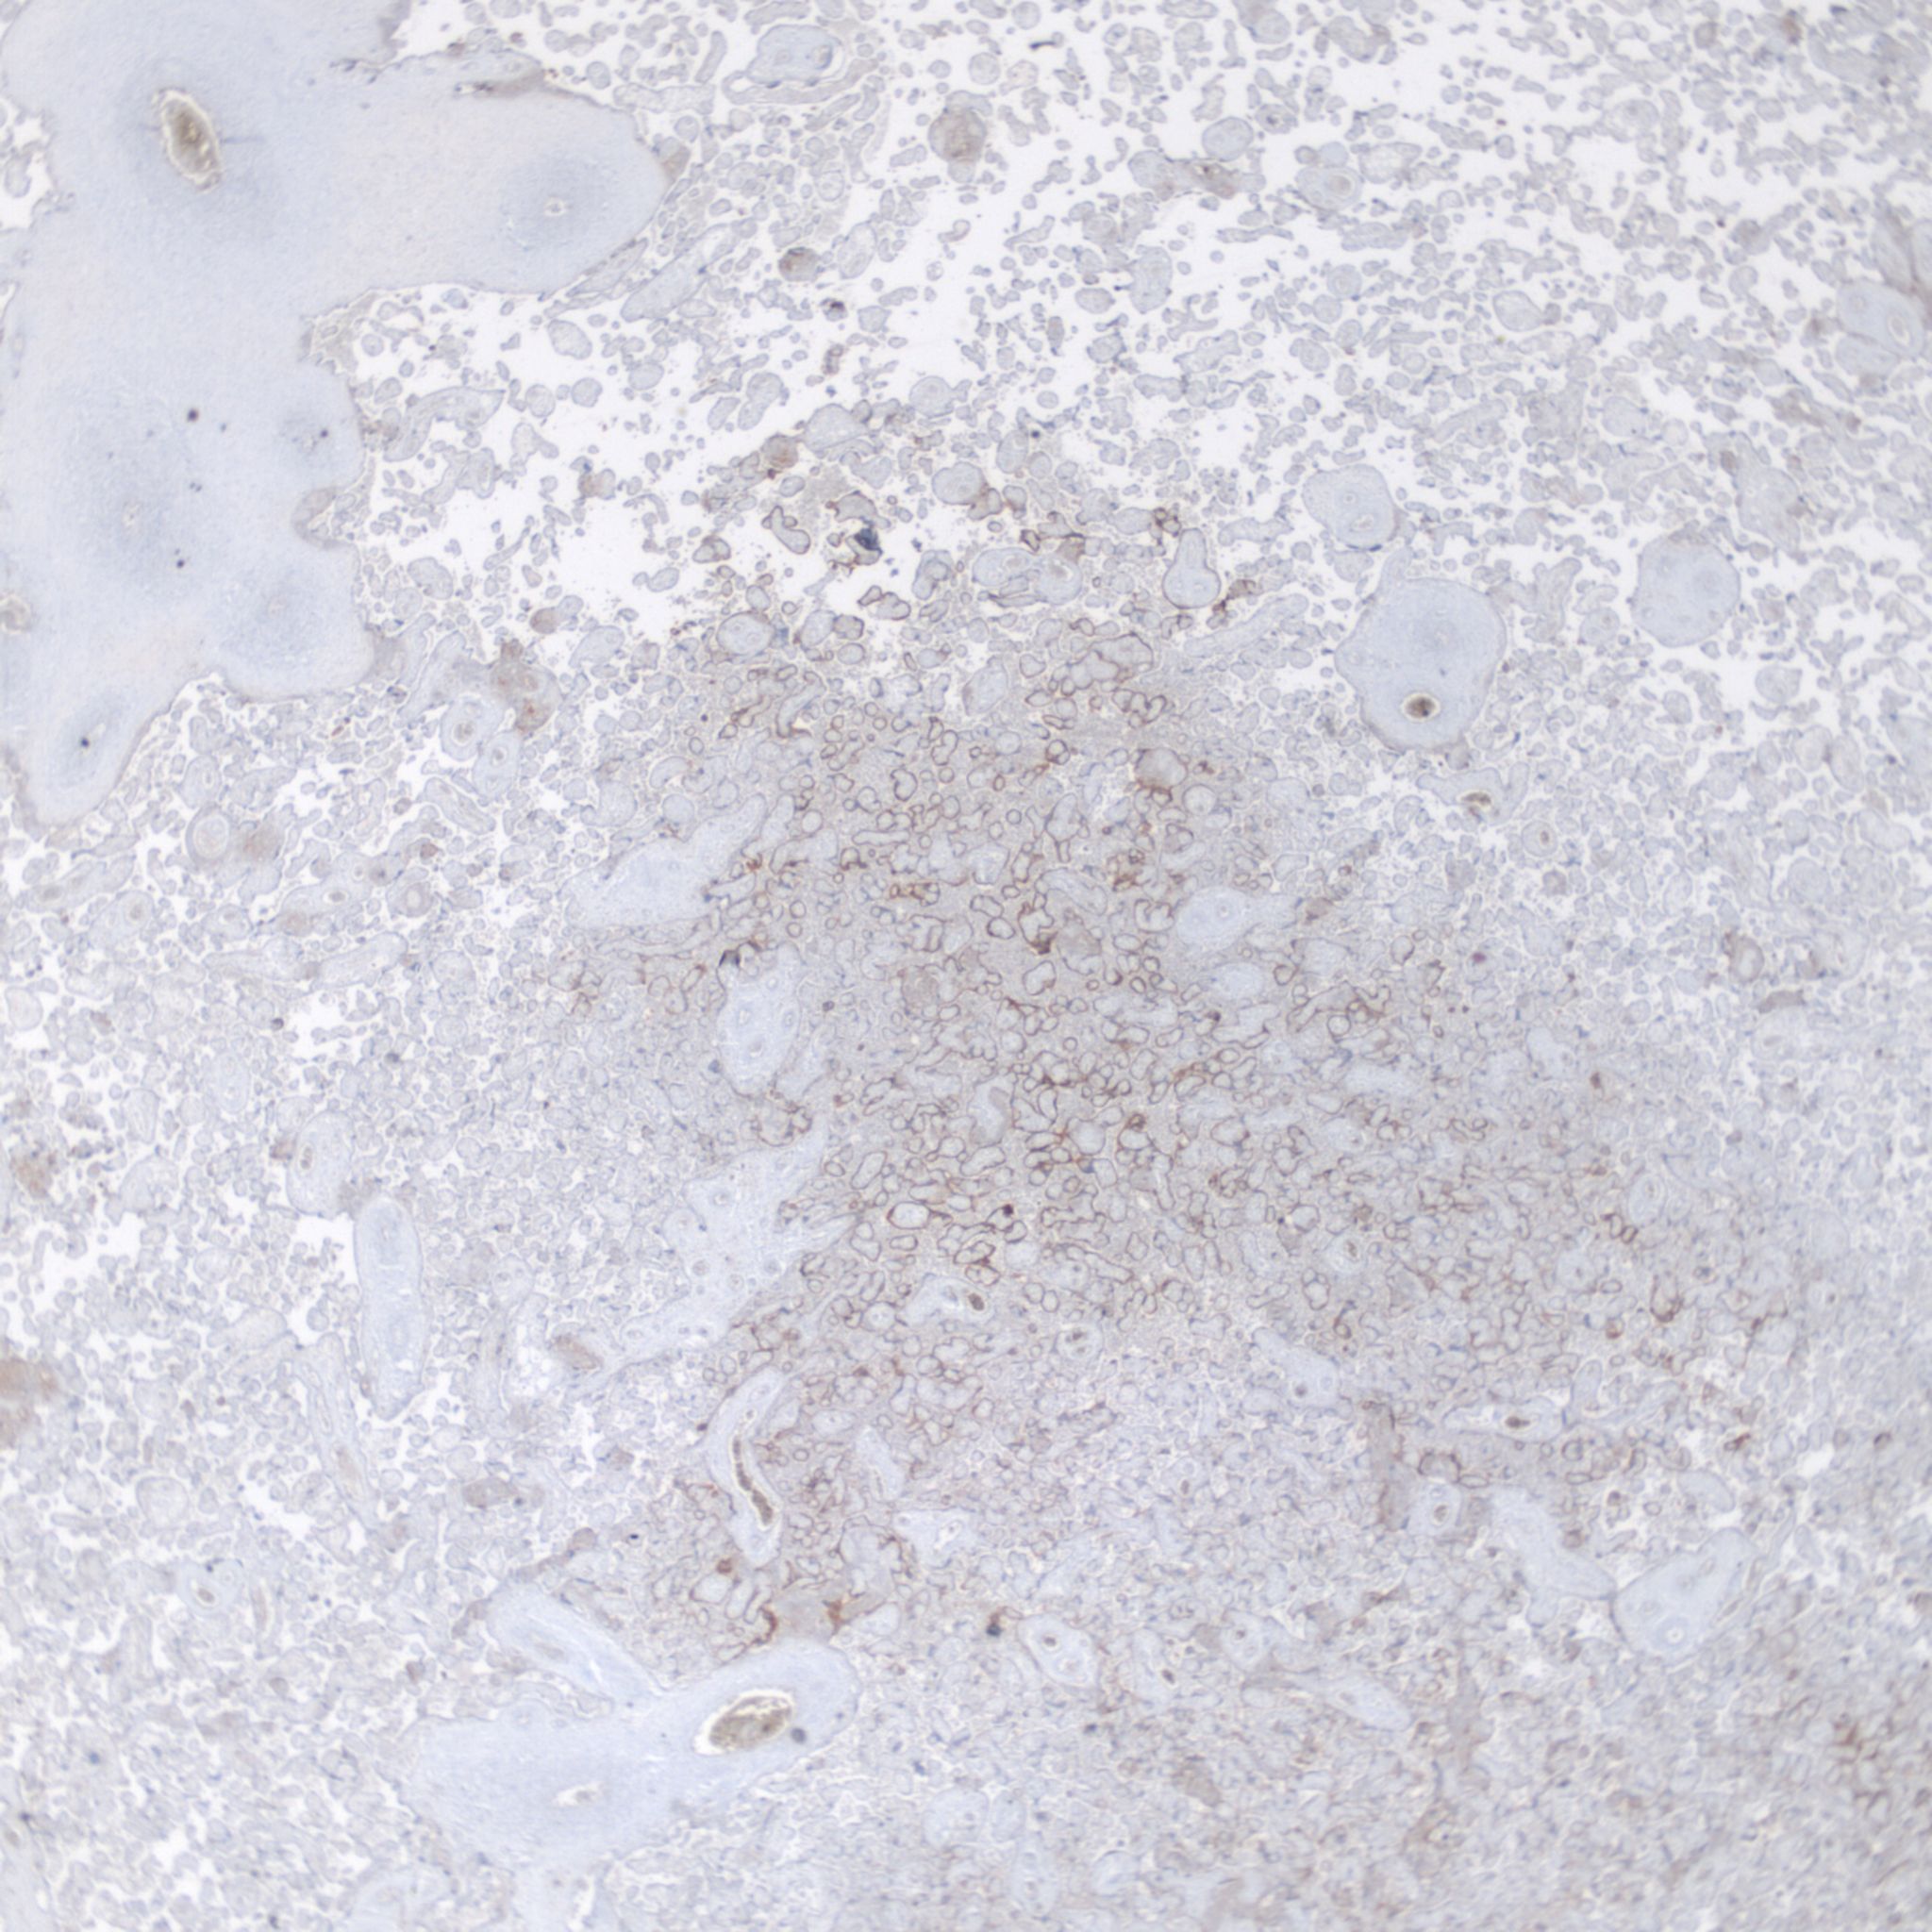

High Grade (massive) CHIV

Low Grade CHIV (5-50% of the intervillous space occupied by monocytes)